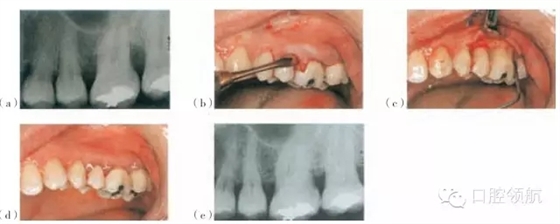

圖26.5 使用Emdogain®和PerioGlas®處理的一個(gè)病例。(a)手術(shù)位點(diǎn)的術(shù)前放射線圖像。(b)頰側(cè)瓣的影像。(c)使用EDTA調(diào)節(jié)器后應(yīng)用Emdogain®。(d)瓣的復(fù)位與縫合。(e)術(shù)后18個(gè)月的放射線圖像

Straumann®, Emdogain也可以被用在骨移植材料的結(jié)合處,例如作為骨沉積的支架(圖26.5)的Bio-Oss®(GeistlichPharma AG),PerioGlas®或者StraumannBoneCeramic 400-700®。Emdogain®還可以與GTR技術(shù)聯(lián)合應(yīng)用。